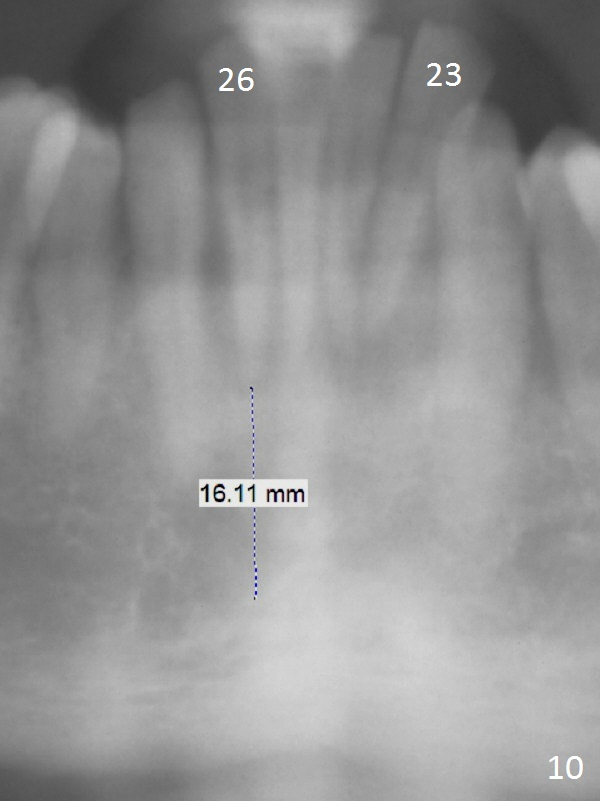

Class II Division II malocclusion (Fig.2,6) will make it difficult to restore #23-26 implant-supported FPD. Although the teeth #7-10 may need to be replaced later (Fig.7,8), enameloplasty will be conducted for #7-10 (Fig.9 white area; Fig.12 black circles (gross reduction)) prior to #23-26 extraction and implant placement (Fig.10). To be flexible in restoration (angulation) and possible future hybrid denture, 2-piece narrow implants will be placed (3.0 or 3.3 mm) instead of 1-piece ones. In fact CBCT shows that the narrowest regular implant (3.8 mm) can be placed in the lower anterior region (Fig.13-15).